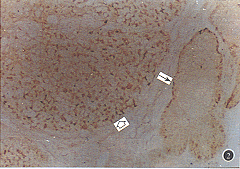

图2 PCNA在睑板腺癌中的表达,在浸润癌中PCNA阳性细胞排列紊乱,呈弥漫分布(空箭头示);正常腺体边缘部增殖旺盛的细胞中可见散在的阳性反应细胞(细箭头示) ×100